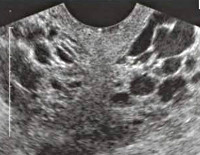

При осмотре наружных гениталий обнаруживаются расширенные поверхностные вены в области вульвы и промежности; при влагалищном исследовании определяется цианоз стенок влагалища, болезненность при пальпации живота. Подтвердить ВРВМТ позволяет сонография органов малого таза, при этом наиболее информативным является комбинированное УЗИ ТА+ТВ доступом. Исследование не только дает возможность выявить органическую патологию, но и с помощью режима ЦДК обнаружить конгломераты варикозно-расширенных вен с измененным кровотоком, патологический рефлюкс крови. По данным УЗДГ сосудов определяется снижение пиковой скорости кровотока в маточных, яичниковых и внутренних подвздошных венах. В рамках оценки флебологического статуса пациента целесообразно провести ультразвуковое ангиосканирование вен нижних конечностей.

С целью изучения локализации и распространенности варикозного расширения вен малого таза, состояния клапанной системы и венозных анастомозов, а также обнаружения тромбов производится чрезматочная флебография. При синдроме венозного полнокровия может быть показана селективная оварикография, предполагающая введение контраста непосредственно в яичниковые вены. При изолированном вульварно-промежностном варикозе используется варикография - контрастирование вен промежности. В настоящее время на смену рентгенконтрастным исследованием приходит КТ органов малого таза, не уступающая им по диагностической значимости. В рамках дифференциальной диагностики, а также при недостаточной информативности перечисленных методов, прибегают к диагностической лапароскопии.